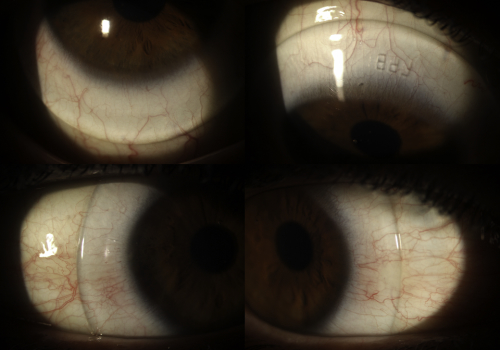

Cue the deafening sounds of aghastment. Fitting an already heathen device to a previously altered cornea? You must be mad! Indeed, in the main orthokeratology ‘bible’; John Mountford’s Orthokeratology: Principles and Practice published back in 2004, there is no mention of fitting orthoK to the post-LASIK cornea (although John is working on a new edition which may address this). A pubmed search shows no articles about orthoK on a post-LASIK cornea. Despite this many experienced orthokeratologists around the world practice ortho-K on the post-LASIK cornea with excellent results. I personally believe there is no more harm in fitting orthokeratology lenses to a lasered cornea than to a virgin example. It is the understanding of most orthokeratologists that the refractive effect of orthoK comes about due to modification of the epithelial cells of the cornea, although the jury is still out in some circles. The following OCT of a patient of mine using orthoK lenses for high myopia illustrates this by showing the thinned epithelium centrally and thickened layer para-centrally. The stroma remains relatively uniform. In contrast all forms of laser refractive corneal surgery involve permanent modification to the stroma of the cornea. The mechanism of refractive change in these two modalities are mutually exclusive. In post-LASIK orthoK the main challenge comes with designing the back surface of an orthokeratology lens to firstly fit the para-central cornea safely and comfortably, and secondly remodel the central epithelium in a way to correct the refractive error. Let’s look at an example:

Anterior OCT showing the thickness profile of the corneal epithelium in myopic orthokeratology. Note this well-fitted lens does not touch the cornea within the treatment zone.